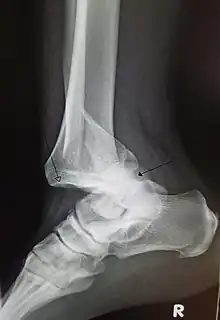

| A traumatic dislocation of the tibiotarsal joint of the ankle with distal fibular fracture. Open arrow marks the tibia and the closed arrow marks the talus. | |

- Foot and Ankle:

- Ankle Sprains primarily occur as a result of tearing the ATFL (anterior talofibular ligament) in the Talocrural Joint. The ATFL tears most easily when the foot is in plantarflexion and inversion.[39]

- Ankle dislocation without fracture is rare.[40]